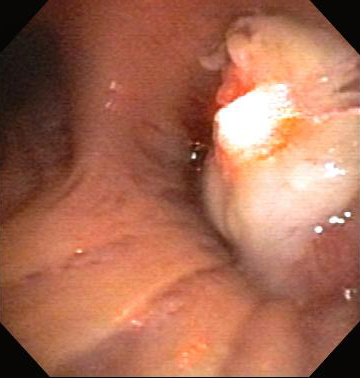

Бронхоскопическая терапия для обструкции нижних дыхательных путей правого главного бронха: аргоноплазменная коагуляция

Из коллекций Хосе Фернандо Сантакруза, дипломированного врача, члена Американской коллегии специалистов в области торакальной медицины, DAABIP, и Эрика Фолка, дипломированного врача, магистра наук; используется с разрешения